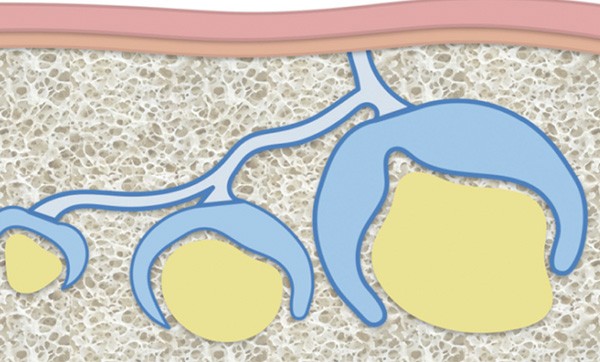

Les molaires permanentes sont issues d’une prolifération du bord libre de la lame dentaire qui évolue en direction distale (fig. 1). La dernière différenciation à apparaître est celle du bourgeon de la troisième molaire [1].

L’éruption des dents de sagesse a donc lieu tardivement, en fin de croissance. Dans un contexte de dysharmonie dento-maxillaire, le manque de place favorise non seulement les malpositions, versions inclusions, mais conduit également à des morphologies souvent complexes des racines qui s’édifient en fonction des contraintes anatomiques.